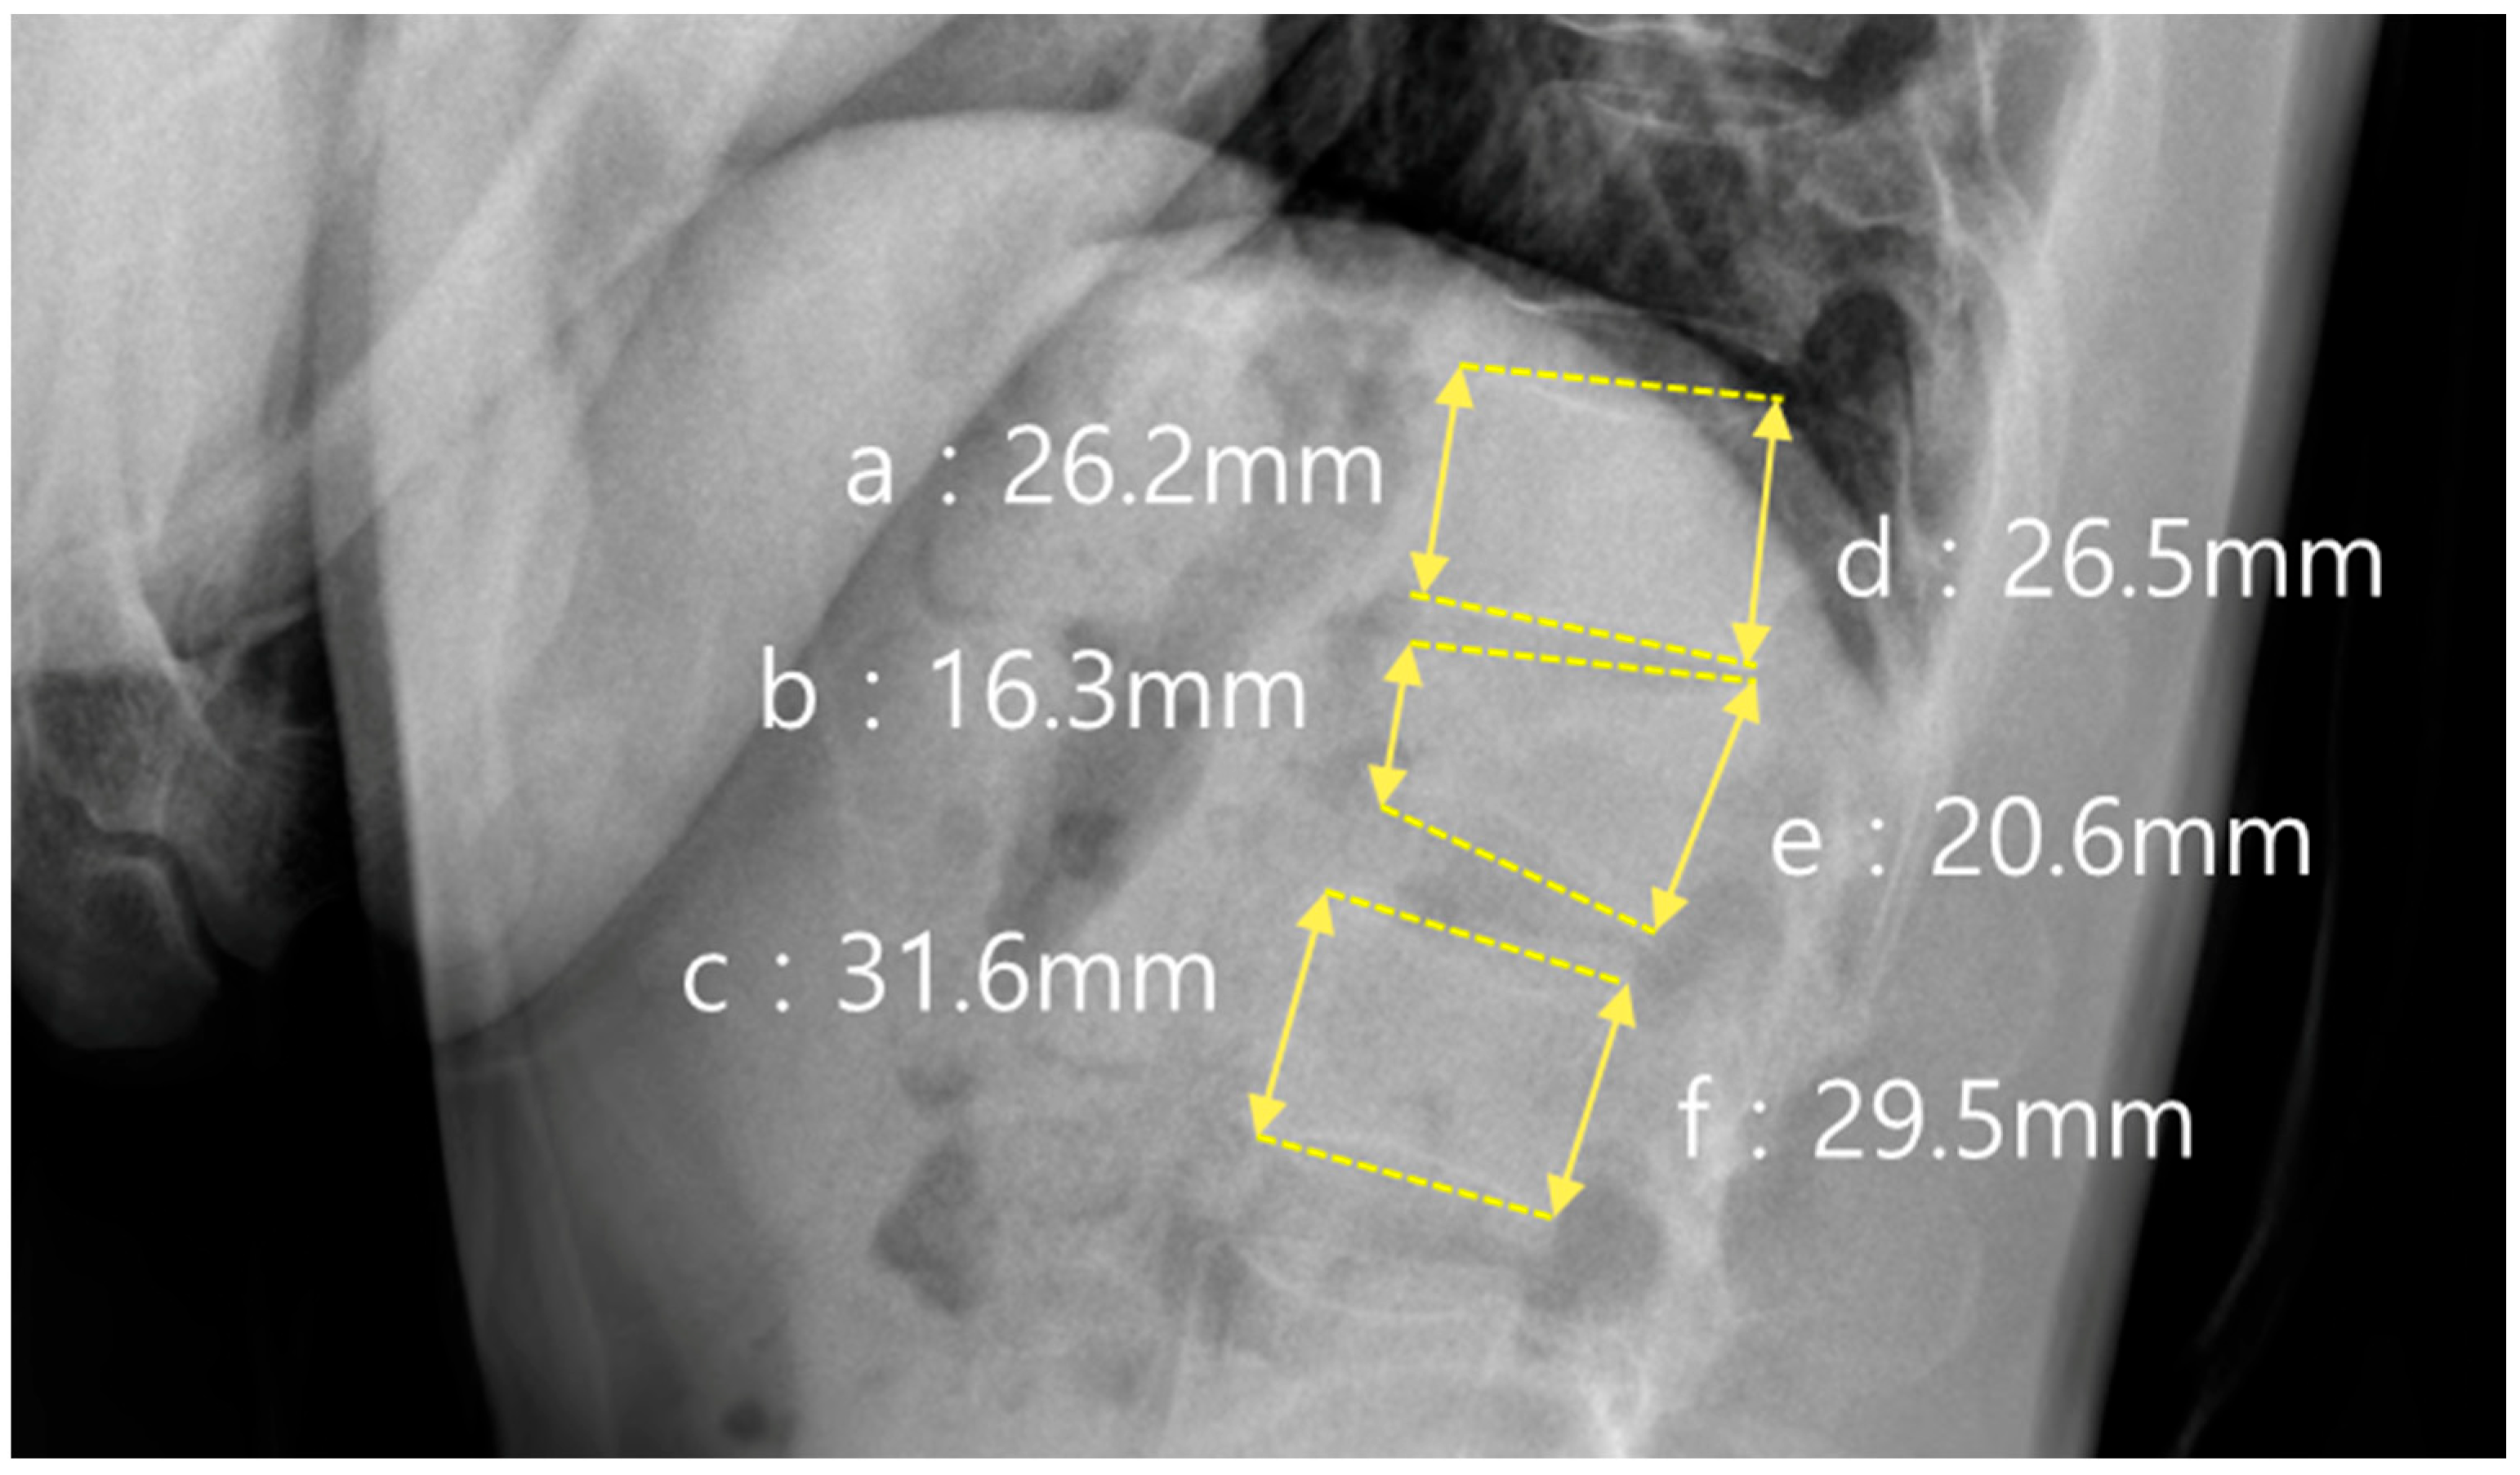

In addition to sagittal alignment, the vertebral body morphology was evaluated using the anterior and posterior vertebral body height ratios, as shown in Figure 3. The anterior height ratio was calculated as (b × 2)/(a + c) × 100, where a and c represent the anterior vertebral body heights of the vertebrae above and below the fracture, respectively, and b represents the anterior height at the fracture level. The posterior height ratio was calculated using the formula (e × 2)/(d + f) × 100, where d and f represent the posterior vertebral heights of the adjacent vertebrae, and e represents the posterior height of the fractured vertebra.

Figure 3. Measurements of vertebral body height ratios. Anterior and posterior vertebral body height ratios were calculated based on the fracture level using the formulas: Anterior ratio = (b × 2)/(a + c) × 100%, Posterior ratio = (e × 2)/(d + f) × 100%. In this figure, an L1 fracture is shown. The anterior body height ratio was 56.3%, and the posterior body height ratio was 73.8%: (a) a level above fracture (anterior); (b) fracture level (anterior); (c) a level below fracture (anterior); (d) a level above fracture (posterior); (e) fracture level (posterior); (f) a level below fracture (posterior).